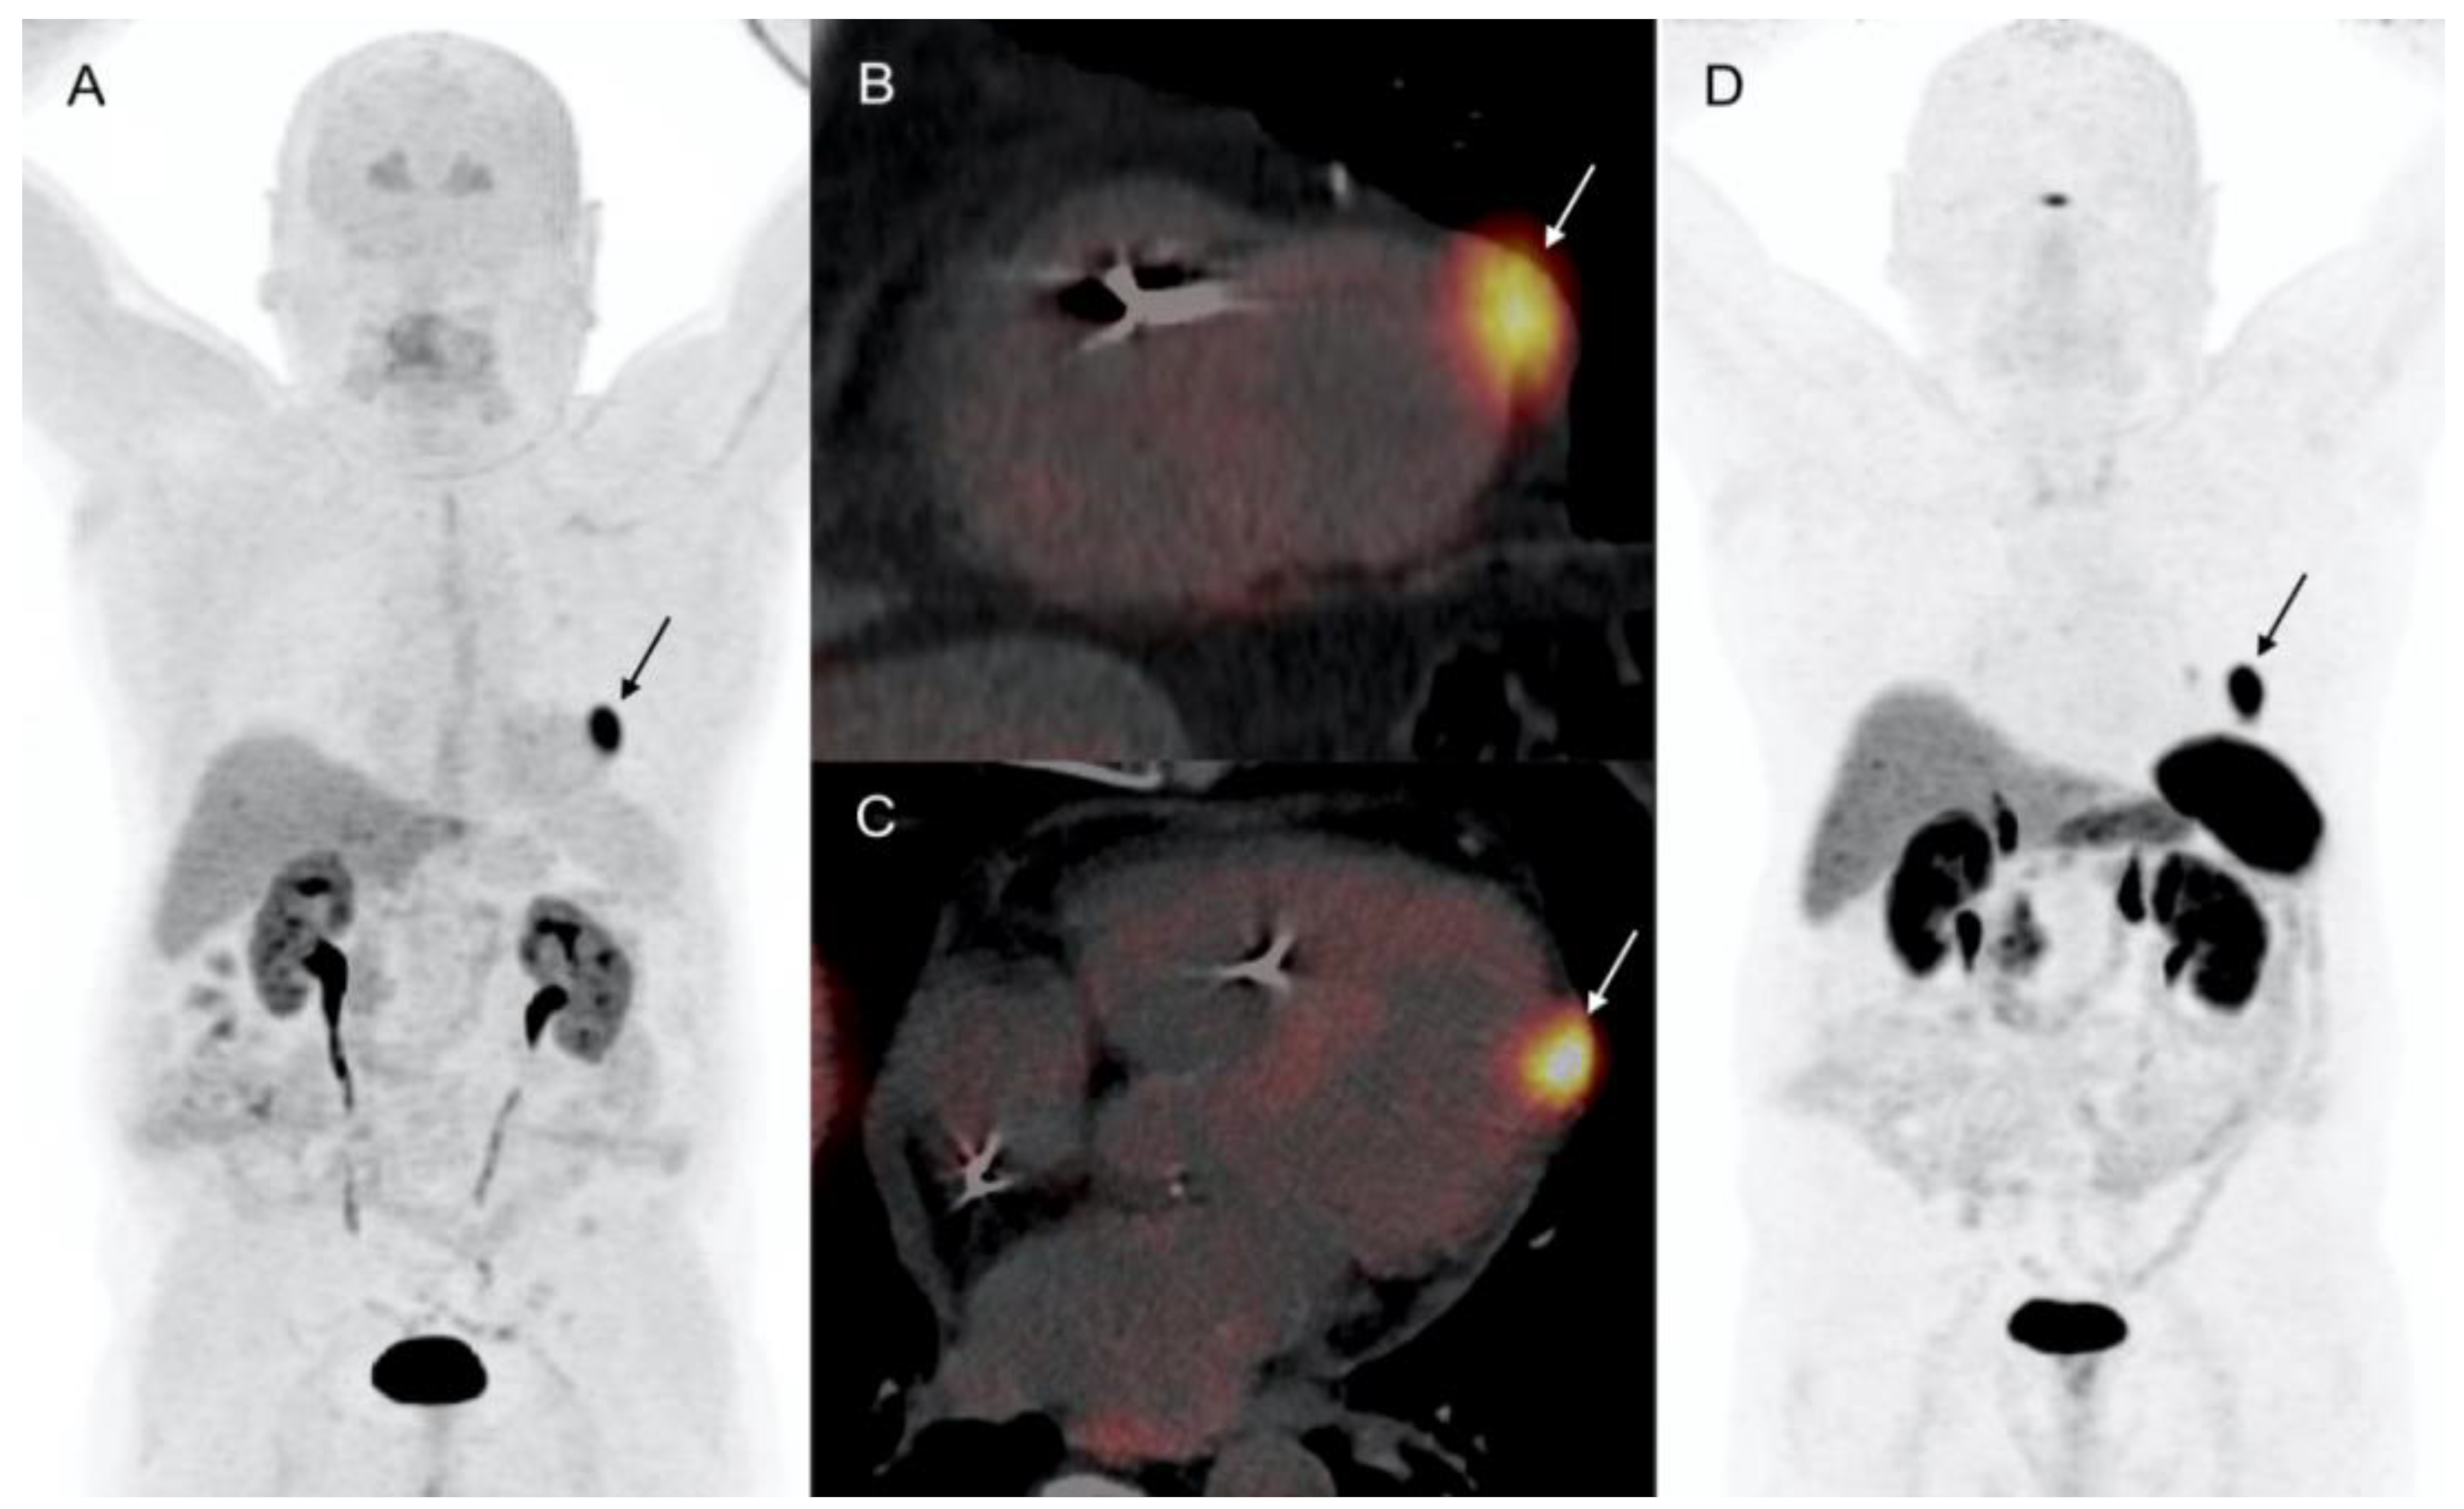

2.1. Patient 1

- 68Ga-DOTA-peptides and 18F-DOPA PET/CT are highly sensitive and specific for the initial diagnosis of CMs, which are usually detected incidentally during routine investigations;